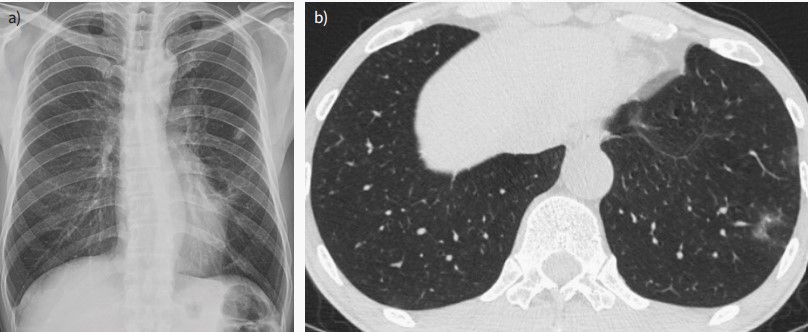

圖1 a無(wú)癥狀患者出現(xiàn)非特異性鈣化結(jié)節(jié),提示左肺上葉陳舊性結(jié)核分枝桿菌或其他非結(jié)核感染。b同一患者13個(gè)月后的CT結(jié)果,患者無(wú)癥狀,隨訪(fǎng)CT顯示雙肺多灶性、邊界不清的磨玻璃樣或?qū)嵭越Y(jié)節(jié)病變。